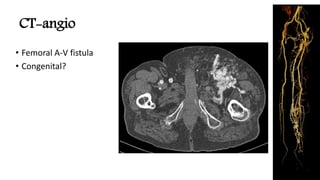

CT-angio

• Femoral A-V fistula

• Congenital?

CT-angio • Femoral A-Vfistula • Congenital?